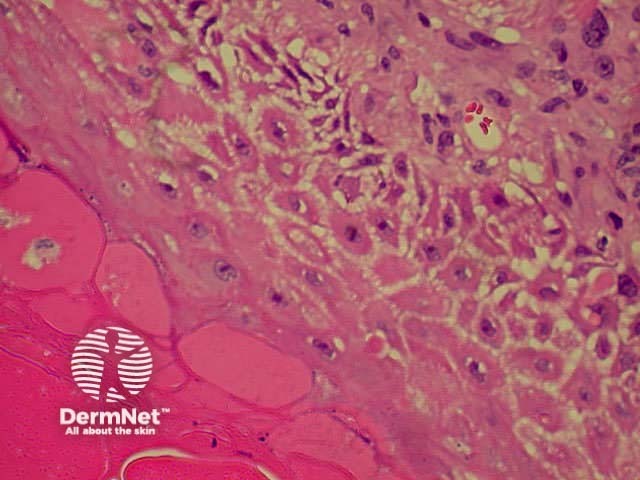

Systemic vasculitis may affect the skin and vascular damage may be the main feature or a secondary feature in several skin diseases. Link to a clinical description of cutaneous vasculitis.

The histological features they have in common are:

Leucocytoclastic vasculitis Leucocytoclastic vasculitis